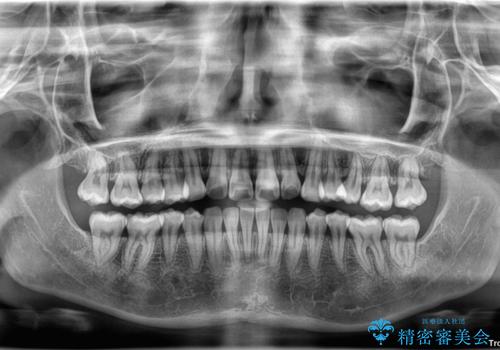

- 左上の前歯が出ていることを主訴として来院された患者様です。

当初はインビザラインを希望されていましたが、職業柄お茶する機会が多く装着時間を確保することが難しいとのことで、相談の上ワイヤー矯正の中では目立ちにくい審美装置で矯正を進めていくこととしました。